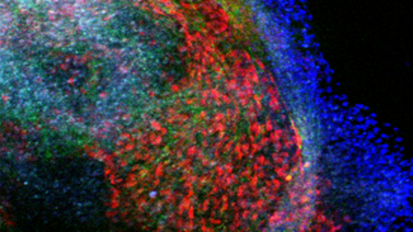

Research Points to Genetic Underpinnings of Olfactory Neuroblastoma

The study, led by Johns Hopkins neurosurgeon-scientists, sheds light on the mechanisms involved in cancer and could lead to new treatments for olfactory neuroblastoma. Image shows cellular image of neuroblastoma.